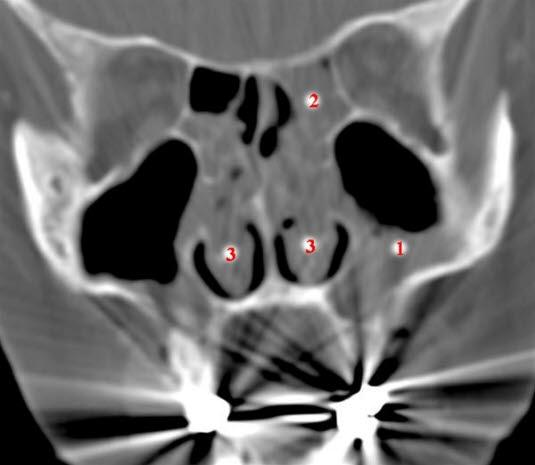

Ved å undersøke nesen din med en lyskilde vil legen ofte kunne se polyppene som gråbleke og skinnende kuler i nesehulrommet. Det kan være flere av dem, og de finnes ofte på begge sider i nesen.

Ved uklarhet om diagnosen kan en CT-undersøkelse avklare om det foreligger polypper og kartlegge omfanget av polypper. Dersom du henvises til spesialist, vil ØNH-legen titte inn i nesen, ofte ved hjelp av et endoskop. I samme seanse kan ØNH-legen om ønskelig også fjerne polyppene gjennom endoskopet.